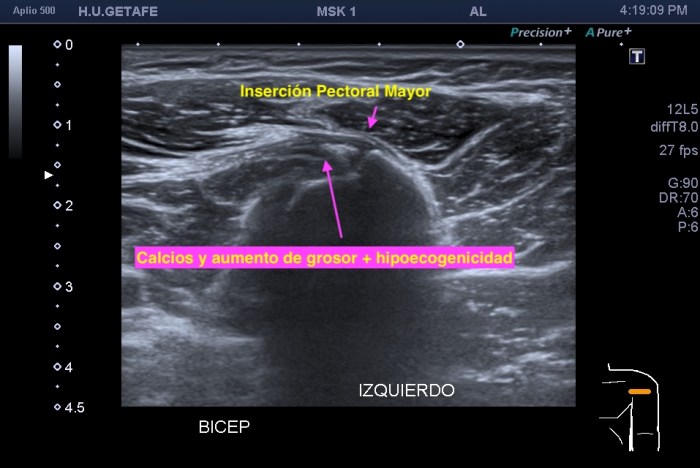

Entensopatías:

• Termino referido a la inflamación que no solo afecta al tendón, también a la inserción ligamentosa, cápsula articular y a la aponeurosis.

• Aumentos de grosor

• Heteroecogenicidad

• Calcios de inserción

• Áreas hipoecogénicas focales

• Erosiones en al cortical del hueso